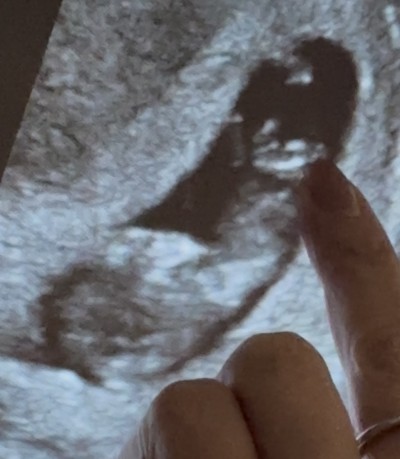

Merhaba kizlar 100de 60 kiz dedi yine gitcem,aşiri halsizlik yorgunluk uyuyorum hep,dondurma pasta aşeriyorum,miyde bulantim aşiri var 2oglumda tam tersiydi,boyle olaniniz varmi?ve soda testide yaptim kabarmadi,kalp atisi 168 sag yumurtalikda tum isaretler kizi gosteriyor

Gebelik haftası 11 hafta 3 gun

Bebeginiz sag tatafta mj solda duruyo gibi gozukuyor

Kaseye gore soyleye bilirmisiniz paylasdim azonce bakin plz

Ne goruyonuzimage